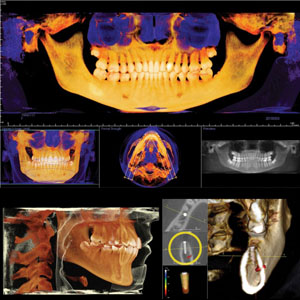

• DVT – 3dimensionale Röntgenbilder (Kopf-CT)

• computergesteuerte Implantatplanung

3d ct